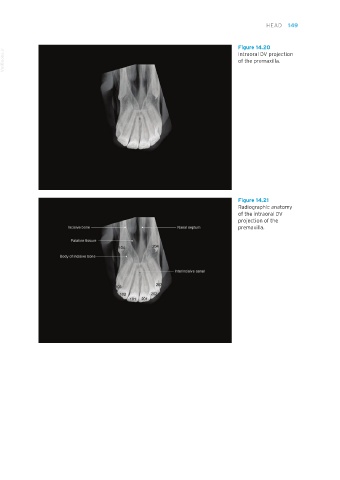

Figure 14.20

VetBooks.ir                                                                        Intraoral DV projection

of the premaxilla.

Figure 14.21

Radiographic anatomy

of the intraoral DV

projection of the

premaxilla.